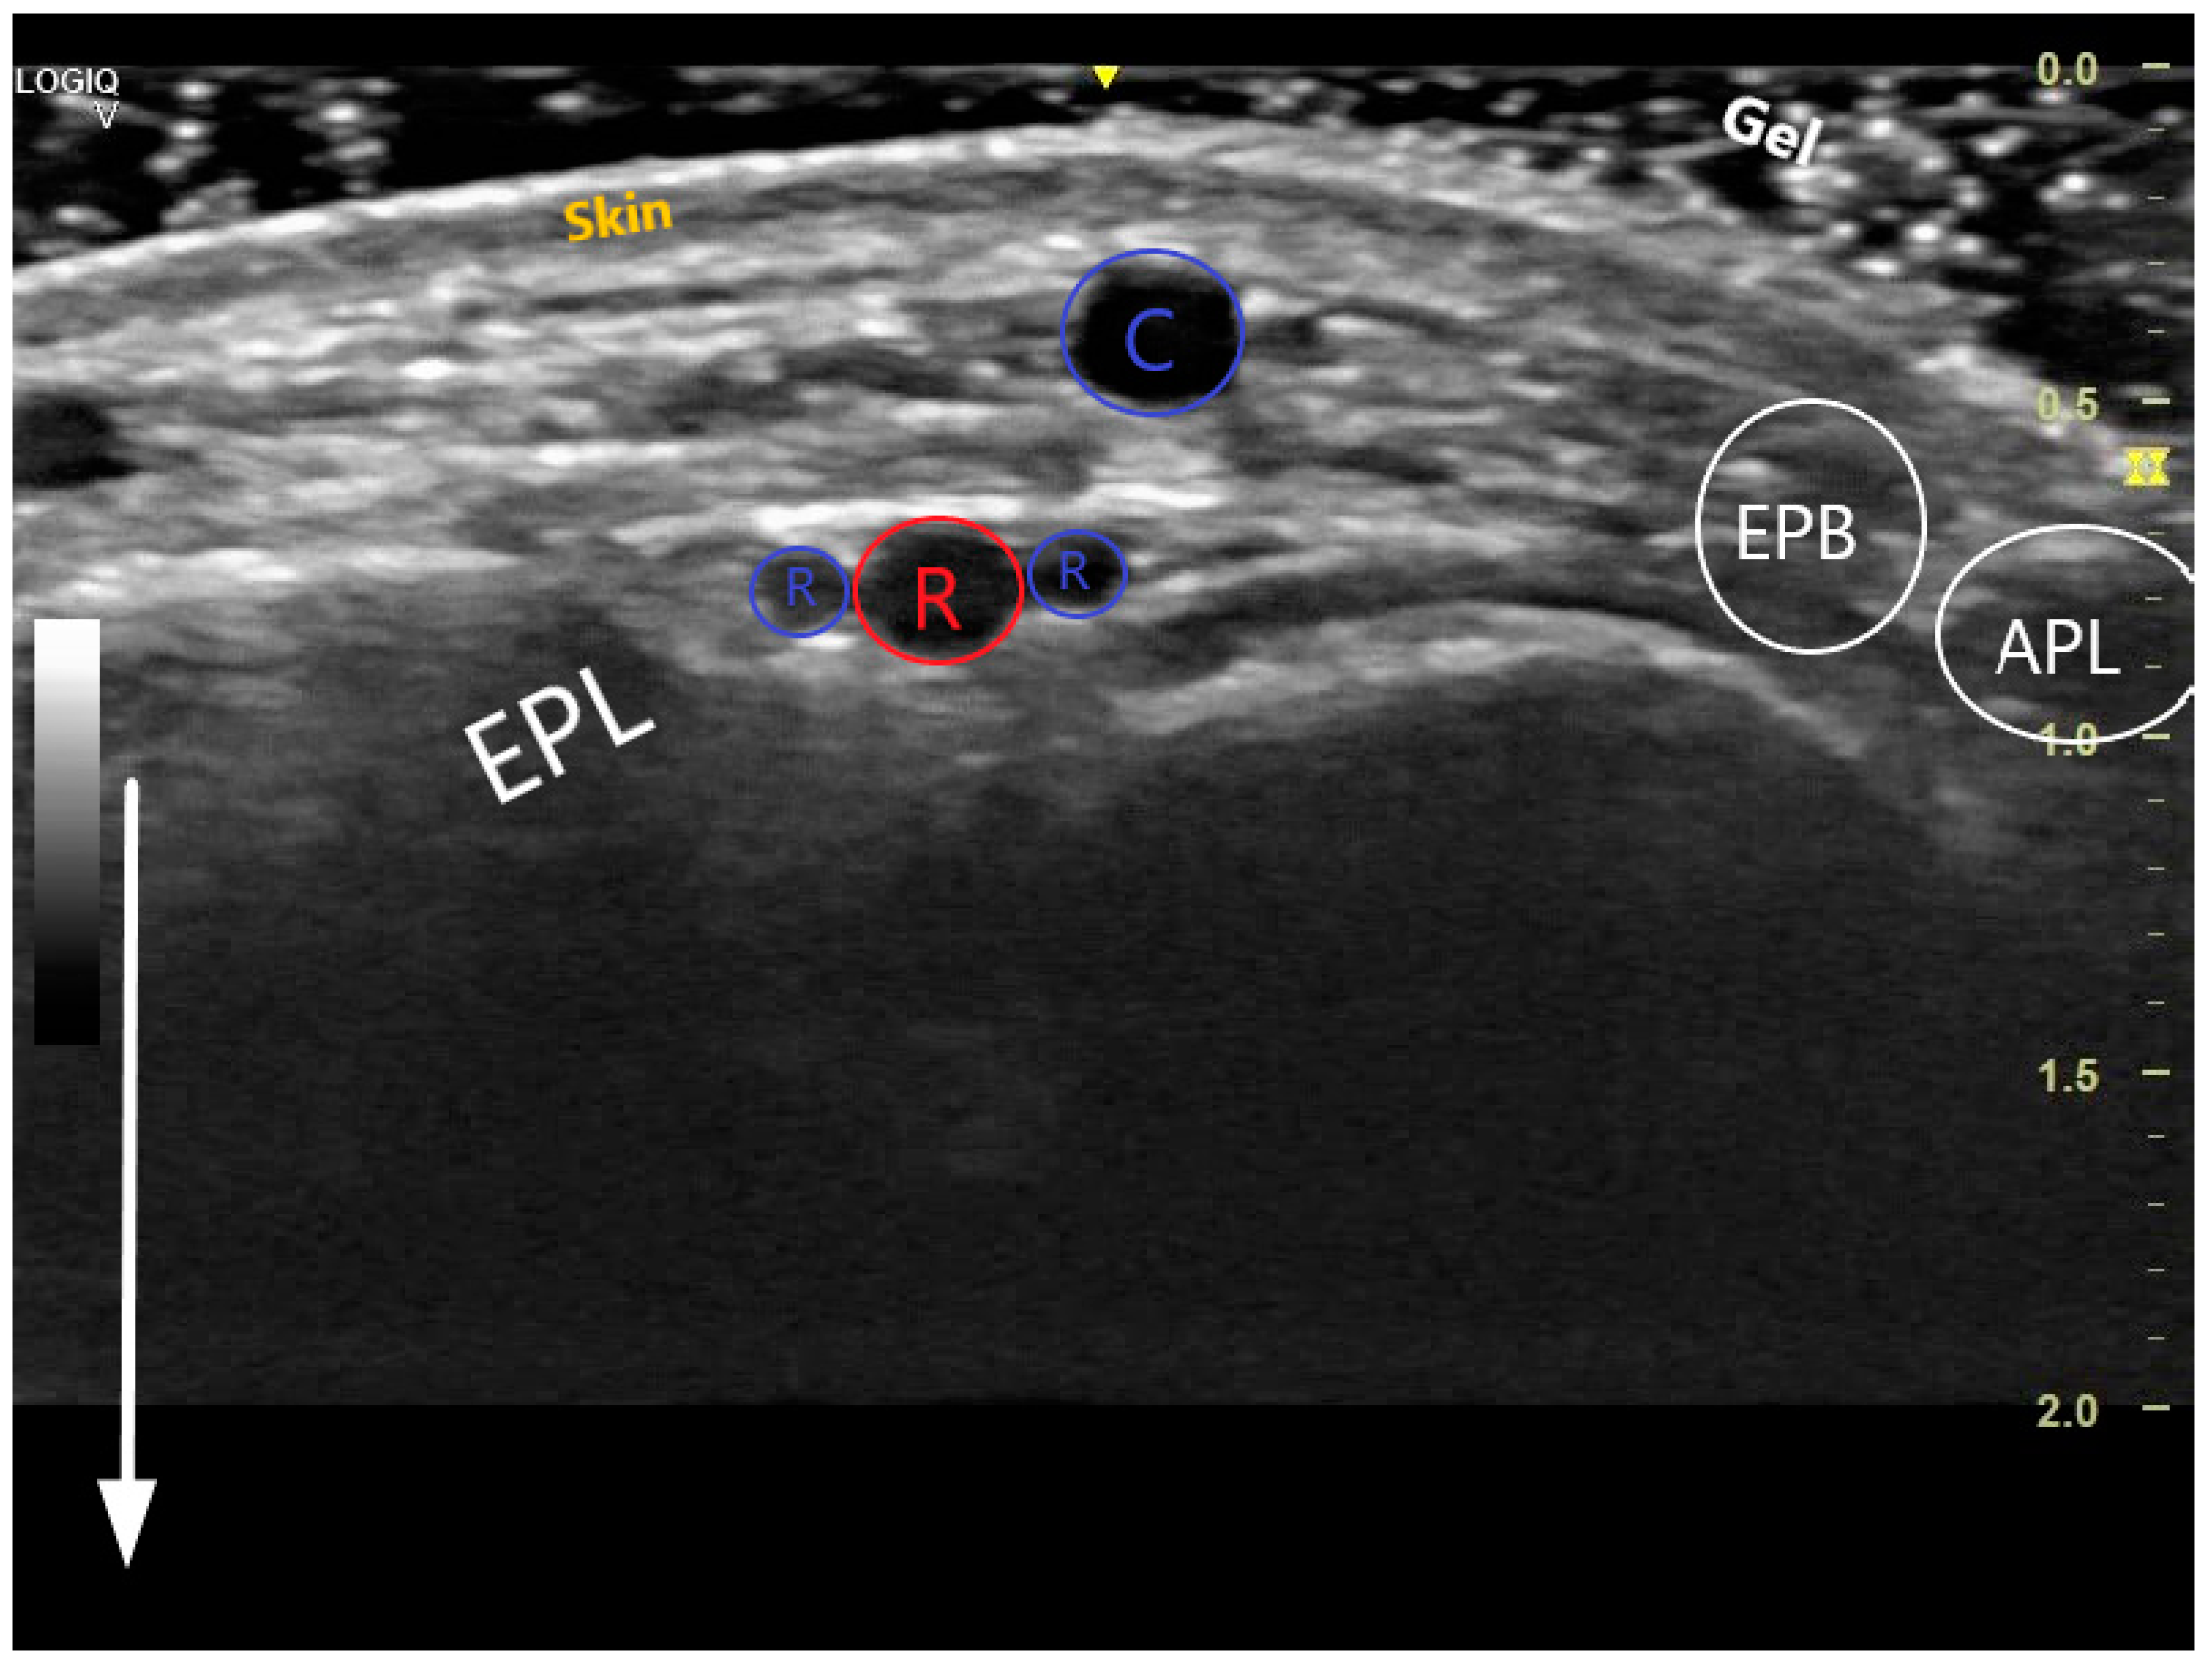

The key anatomical structures that should be identified in the anatomical snuffbox are illustrated in Figure 2. The radial artery should be scanned along the snuffbox in the short-axis view and then switched to the long-axis view in order to select the best site for puncture, aiming for sufficient caliber (ideally > 1.8 mm) and the absence of tortuosity and disease. The common long-axis view is exemplified in Figure 3 along with other pathological variants of reduced or increased peak systolic velocities. The puncture area (the triangle) is separated in two by the tendon of the extensor pollicis longus muscle, which is prominent and easily palpable, and which impels the operator to puncture distal or proximal to it. The true snuffbox area is proximal to the tendon of the extensor pollicis longus muscle, as illustrated in Figure 1 (blue arrow) and Figure 2 where the artery is located laterally to the tendon. The artery then continues under the tendon, actually entering the first intermetacarpal space where it can be palpated and punctured again (dorsum of the hand area—not so preferred among operators, Figure 1, yellow arrow), and finally, it continues its course medially and deeply, forming anastomoses with the ulnar artery. The skin is then punctured parallel to the probe in the exact center of the probe.

Figure 2. Transversal US image at the anatomical snuffbox. The depth has been adjusted so that the structures near the transducer form the majority of the image. The white arrow demonstrates the near and the far during scanning. The 3 layers of the skin are visible, superficially is the cephalic vein (C), deeper the radial artery (red R) accompanied by 2 radial veins (blue Rs). The snuffbox is surrounded by the extensor pollicis longus (EPL), extensor pollicis brevis (EPB), abductor pollicis longus (APL), and scaphoid (S).

The probe is placed on the wrist at the level of the anatomical snuffbox. The visualization of the vessels can be improved by adjusting the depth on the ultrasound machine to the minimum depth and adjusting the gain. The examiner’s hand should rest partially on the patient, and only light pressure should be applied to the soft tissues. The vigorous pressing of the transducer leads to the compression of the artery. The artery is visualized as an anechoic or dark circle that can be distinguished from veins based on the pulsation of the vessel. Manual compression, pulsed wave Doppler, and colour flow Doppler are additional tools that ease the detection of the artery. The transverse (short-axis, cross-sectional) ultrasound view is easy to obtain and is best for identifying veins and arteries and their orientation to each other. The long-axis (longitudinal, in-plane) ultrasound view is technically more difficult to obtain, but the entire needle is continuously imaged, ensuring accurate intraluminal placement. At our institution, the longitudinal method is preferred for cannulation. During the early stages of US use, a learning curve is to be expected; however, this should not dissuade operators from using this valuable know-how. Basic expertise in PRA is needed before moving to DRA but no prior US experience is mandatory. One common error is that once the needle punctures the skin, it is no longer helpful to inspect the wrist. The operator should instead watch the ultrasound screen and move the probe to search for the needle tip.